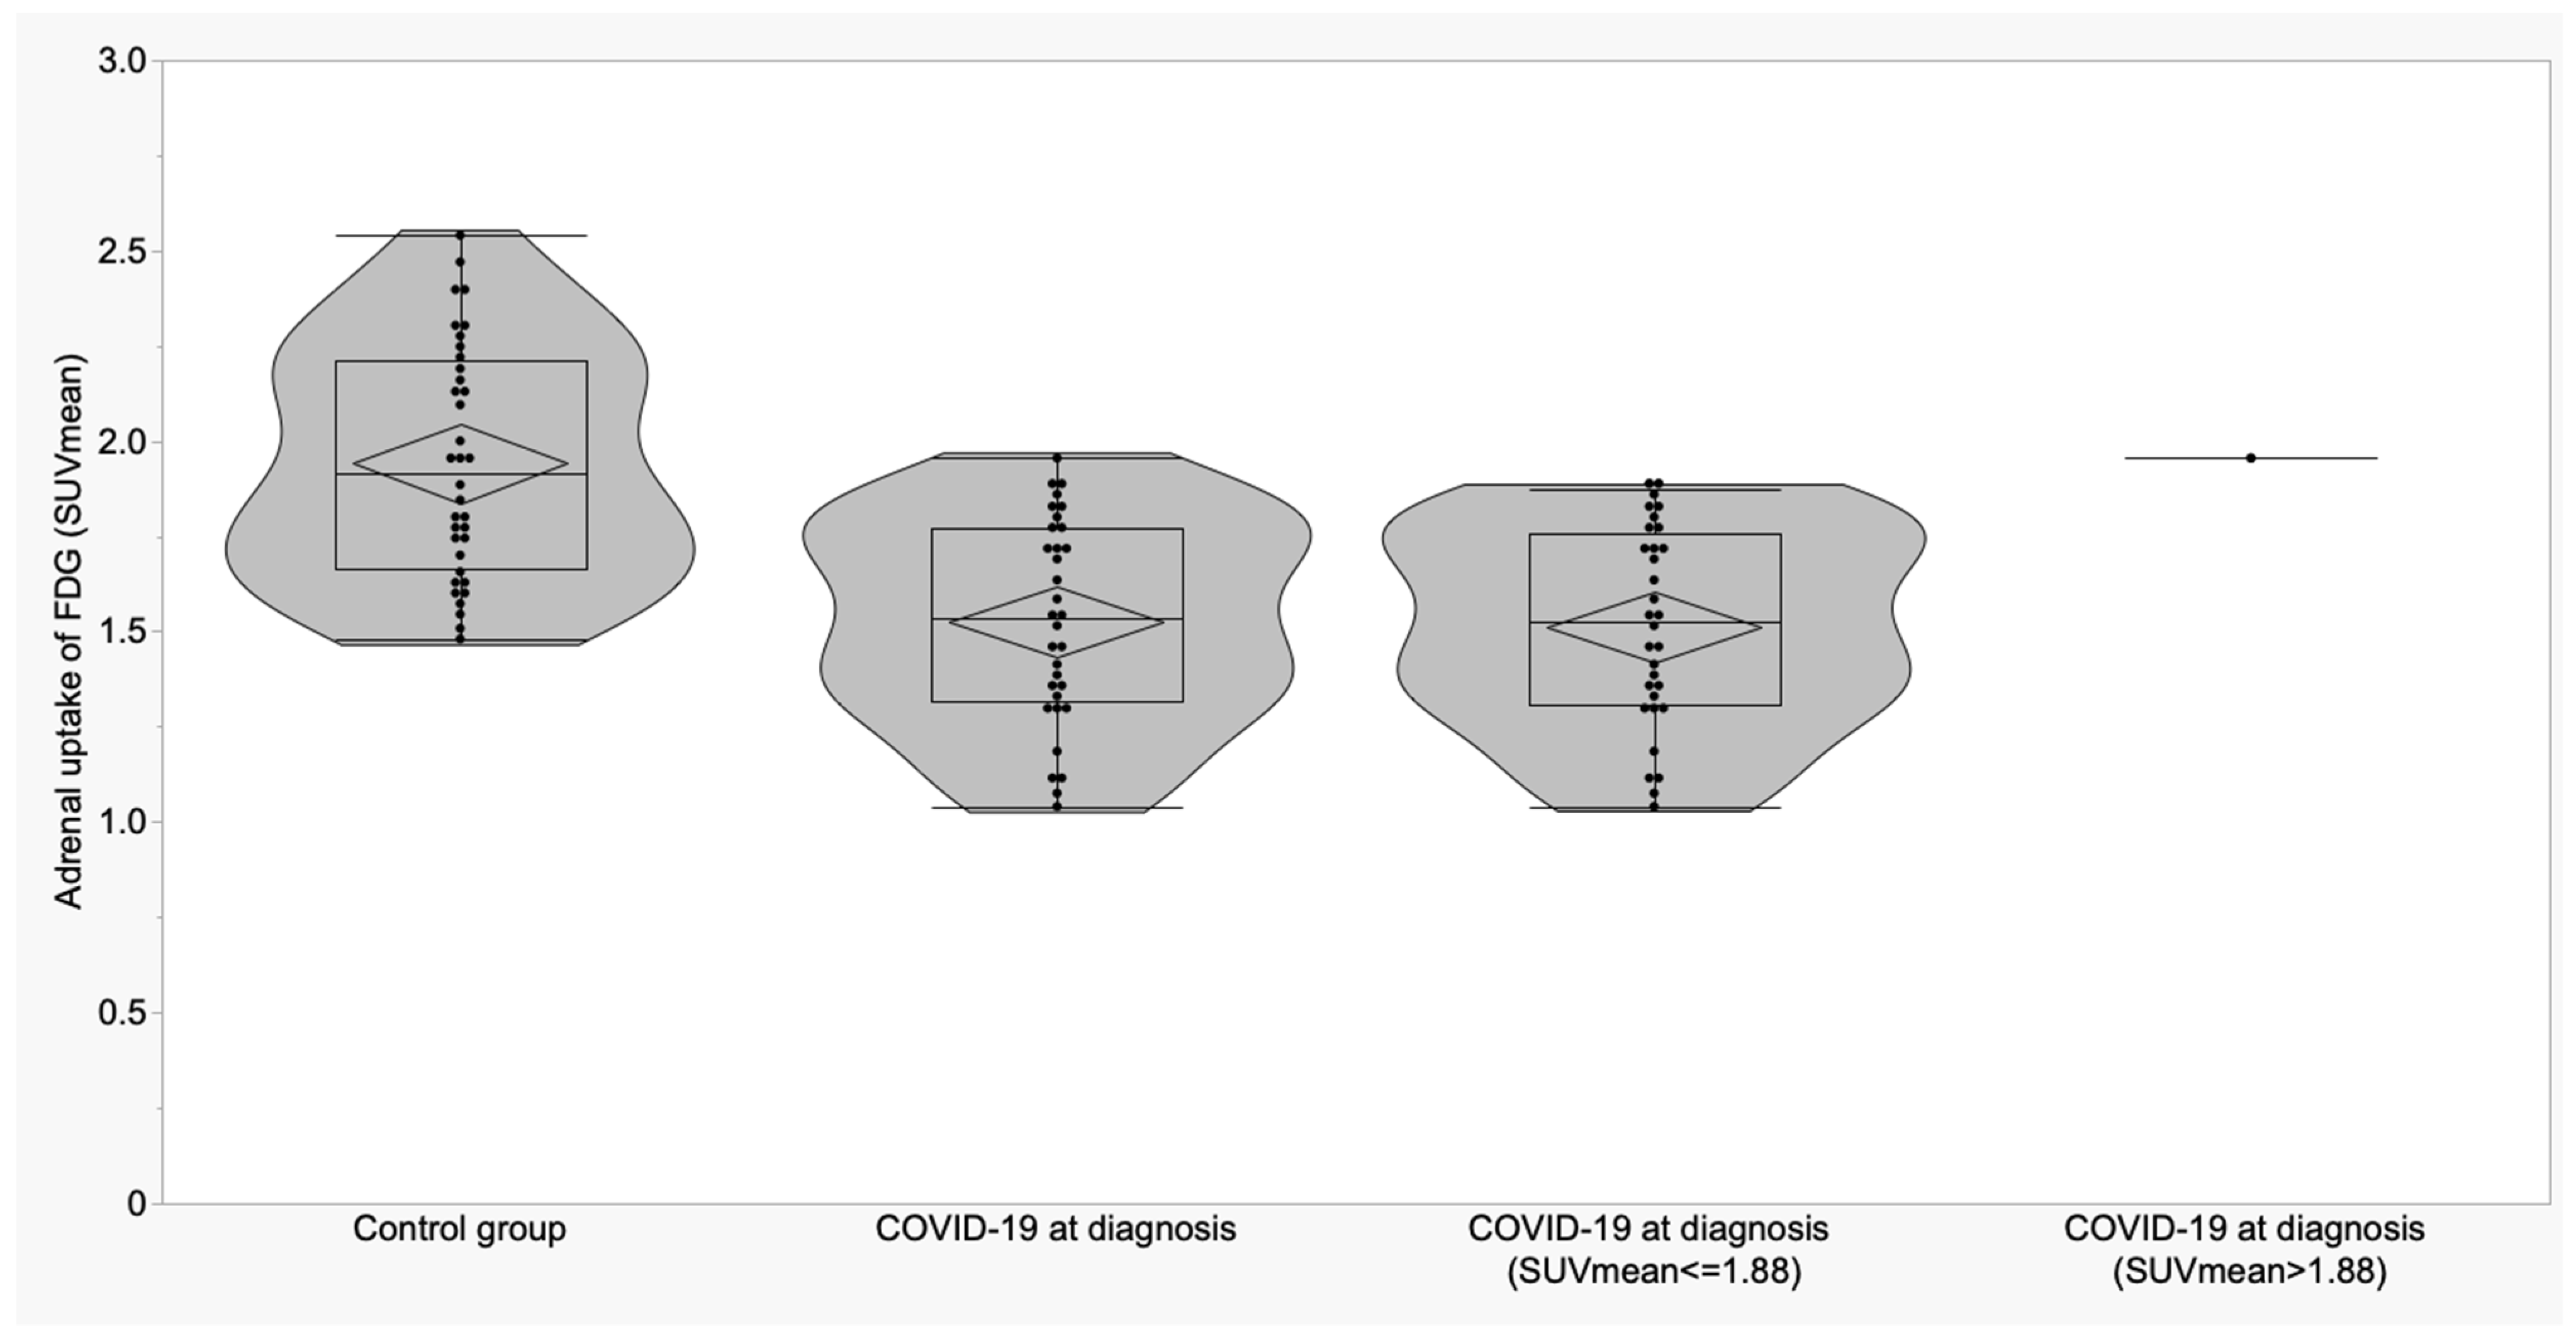

3.2. Thyroid and Adrenal Gland Analysis

| Adrenal (SUVmean) | 1.94 ± 0.30 (1.84 to 2.04) | 1.51 ± 0.27 (1.40 to 1.61) | 1.64 ± 0.23 (1.35 to 1.93) | <0.0001 | <0.0001 | 0.03 | 0.34 |